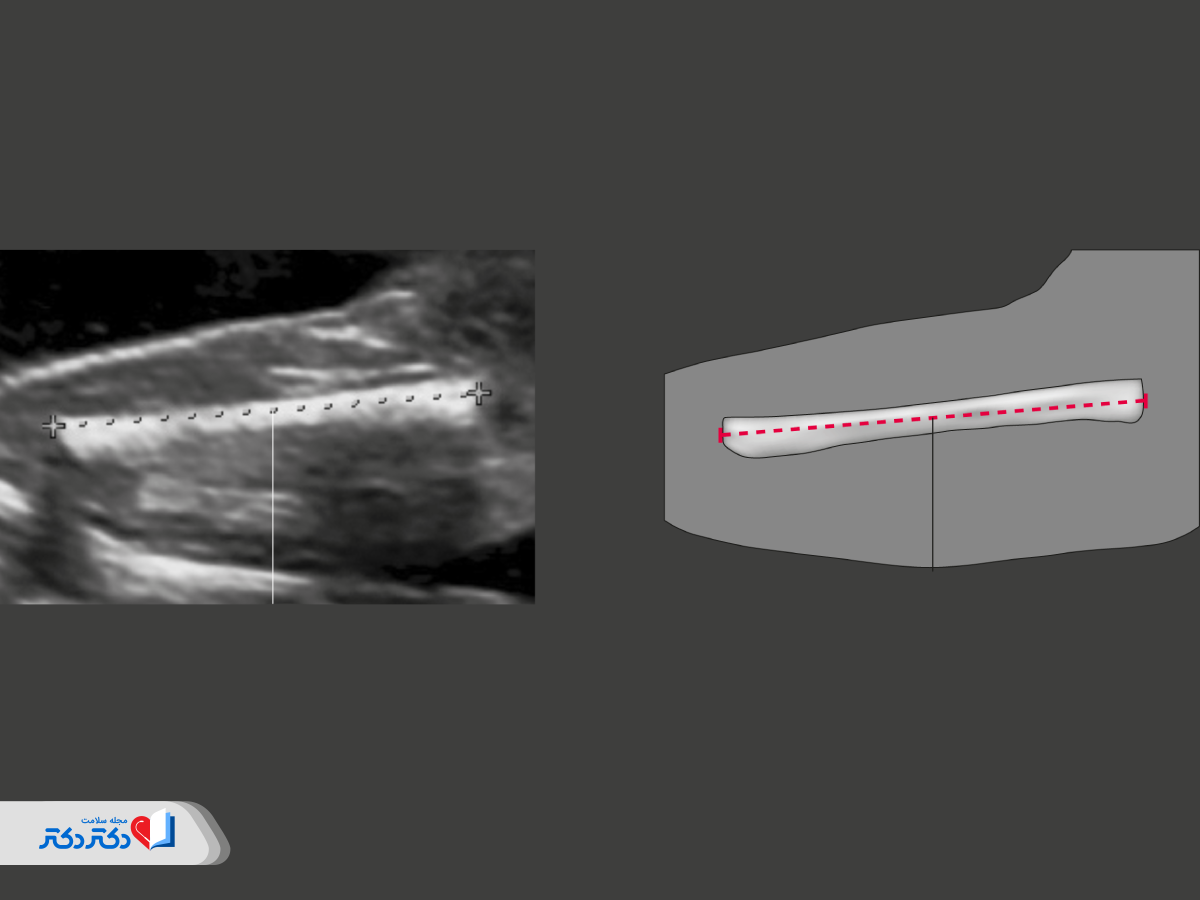

پزشک رادیولوژی علاوهبر اندامهای مهمی مانند مغز و قلب، کلیه و کبد و ریه، اندامهای زیر را بررسی و طول برخی از آنها را اندازهگیری میکند تا میزان رشد جنین مطابق با سن بارداری ارزیابی شود:

- سر؛

- گردن؛

- بازوها؛

- دستها؛

- پاها؛

- انگشتها.